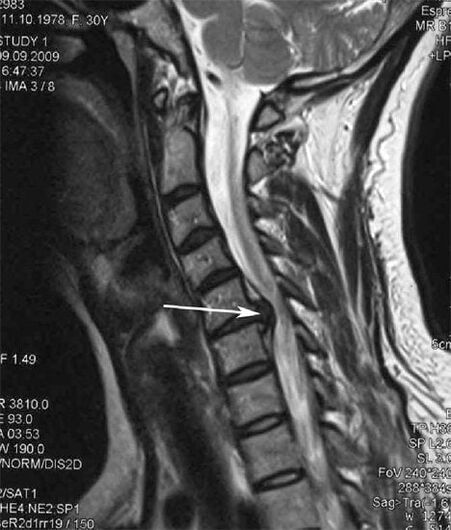

Dans les premiers stades, l'ostéochondrose est détectée par IRM. Plus tard, la pathologie peut être diagnostiquée par radiographie. Sur les radiographies de la colonne cervicale, une diminution de la distance entre les vertèbres, des modifications pathologiques des facettes articulaires et une ostéophytose deviennent perceptibles.

De nombreuses personnes se plaignent de ne pas pouvoir tourner le cou en raison d'une douleur intense qui apparaît après avoir soudainement soulevé quelque chose de lourd. Ce phénomène indique la formation d'une hernie discale. La cause des douleurs dans le dos, le cou et les membres supérieurs est le pincement d'une des racines nerveuses émergeant de la moelle épinière.

| Ostéochondrose cervicale | L'apparition de changements pathologiques dans un ou plusieurs segments de mouvement de la colonne vertébrale. Mobilité vertébrale altérée, développement de syndromes douloureux myofasciaux et pincement des racines vertébrales | Douleurs, paresthésies et troubles moteurs dans la région cervicale, qui se propagent à l'arrière de la tête et aux membres supérieurs. Détection de changements caractéristiques de la colonne vertébrale sur l'IRM et les radiographies (ostéophytes, diminution de la distance entre les vertèbres, signes de lésions des articulations intervertébrales) |